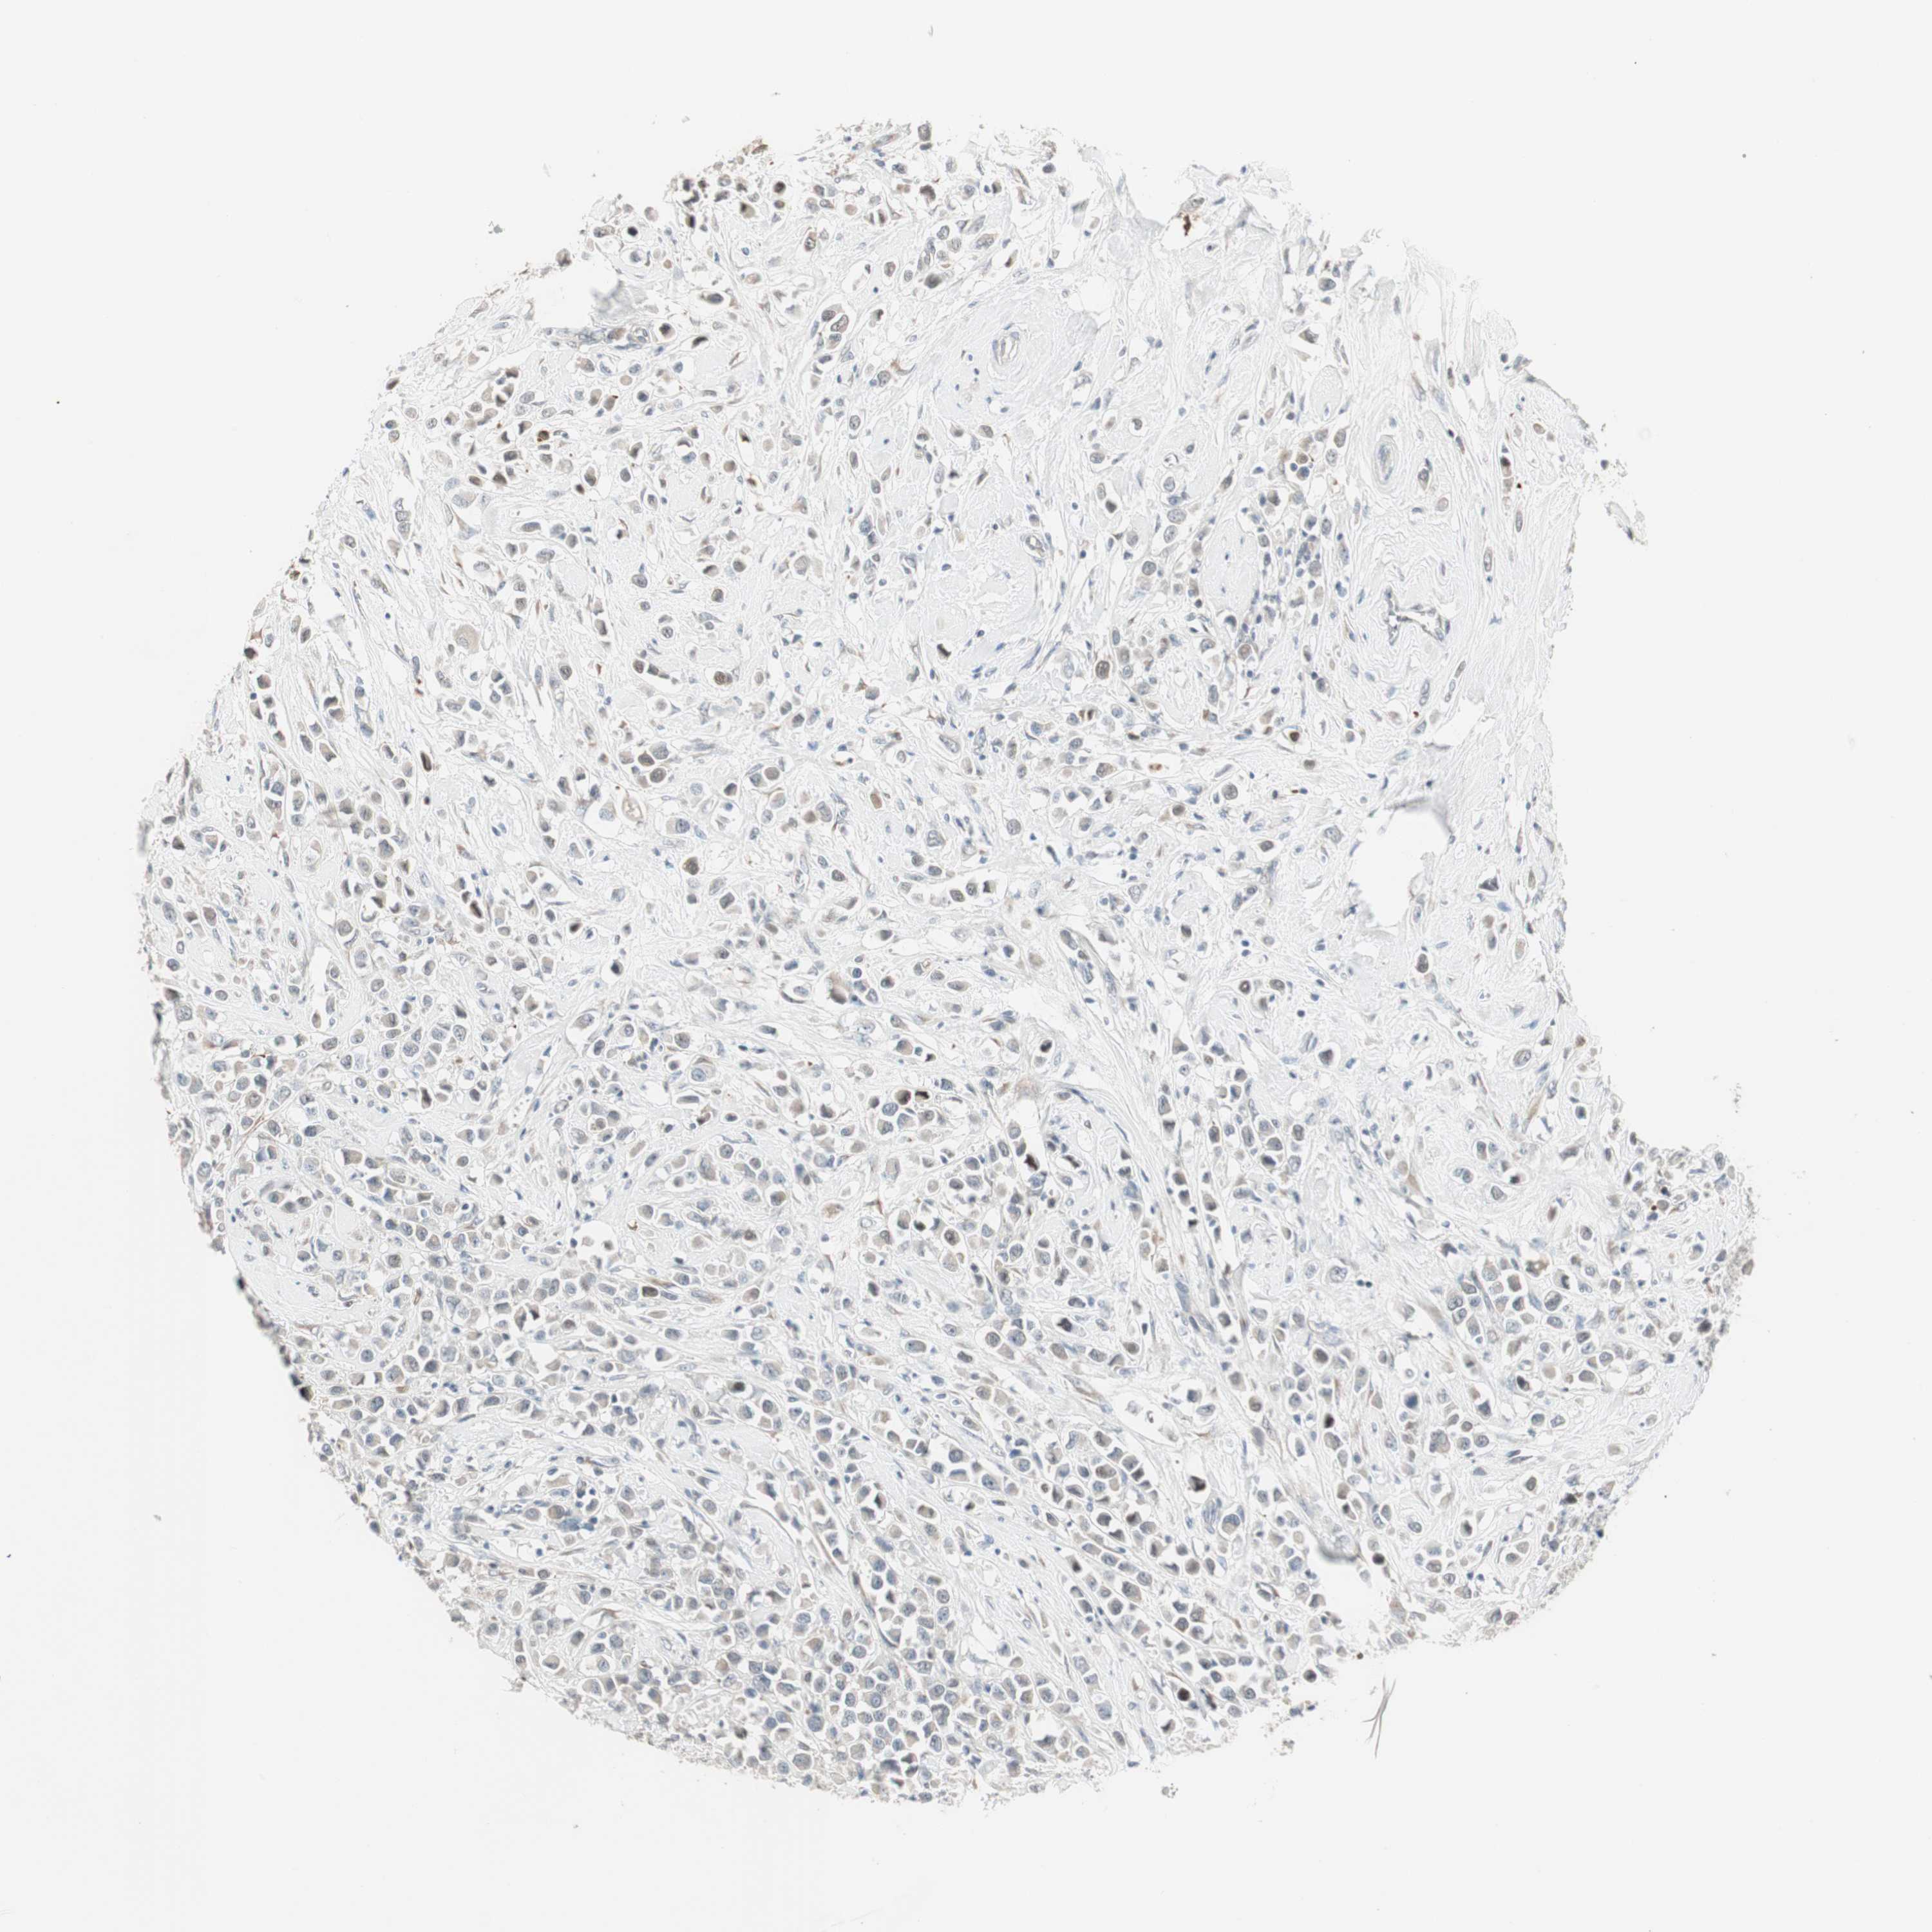

CANCER BREAST CANCER Show tissue menu

BRCA TCGA BRCA VALIDATION PROTEIN EXPRESSION